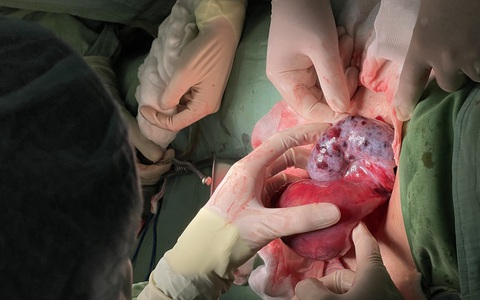

Một bé gái 15 tuổi bị u buồng trứng nhưng gia đình không hay biết, đến khi bị biến chứng xoắn, bé được đưa vào bệnh viện trong tình trạng đau bụng dữ dội.